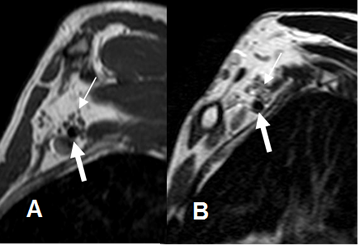

Fig 5. Raíces normales.

A: RM sagital en T1 y B: RM sagital en T2. Raíces normales (Flechas delgadas), por encima de los vasos subclavios. (Flechas gruesas).